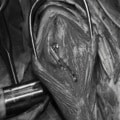

関節鏡検査を実施いたしました。関節鏡検査では、重度の滑膜炎および前十字靭帯の完全断裂が認められました。半月板に損傷は認められませんでした。

断裂前十字靭帯の除去を行いました。その後 TTA(Tibial tuberosity advancement)を実施しました。

写真の膝関節の垂直線を綿棒の木柄が表しており、遠位の脛骨粗面との位置関係が平行ではありません。

断裂前十字靭帯の除去を行いました。外側方向からのテンションが著しく、外側広筋と膝関節外側支帯の解放を行いました。膝関節伸展機構の著しいアライメント異常が認められたため、脛骨粗面転移術を実施しました。

転移側の骨床は犬種特有の変形した表面であったため、転移後の骨片の圧着状態が改善するように変形表面をラウンドバーにて切削しました。滑車溝の著しい低形成が認められたため、滑車溝形成術を実施いたしました。